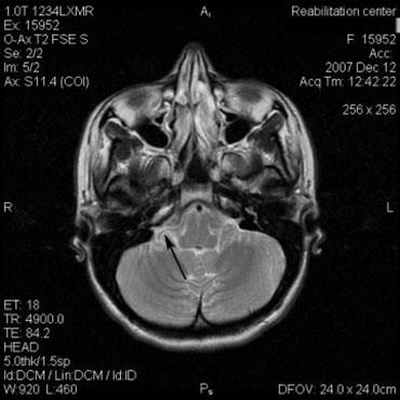

(Слева) При аксиальном исходном изображении (МРА) у пациента с спазмом правой половины лица визуализируются извитая правая позвоночная артерия и ЗНМА, воздействующие на область выхода корешка лицевого нерва. В цистерне мостомозжечкового угла (ММУ) визуализируется лицевой нерв.

(Справа) При аксиальной МРТ CISS на уровне цистерн ММУ у пациента с правосторонним гемифациальным спазмом определяется петля ЗНМА, смещающая ЧН VII в цистерне ММУ кзади, в результате чего он «свешивается» с заднего края слухового отверстия.

(Слева) При аксиальной МРТ CISS у пациента с левосторонним гемифациальным спазмом визуализируется петля левой позвоночной артерии, выдающаяся в цистерну ММУ, где она воздействует на проксимальную часть лицевого нерва в области выхода корешка.

(Справа) При аксиальной МРТ Т2 ВИ у пациента с гемифациальным спазмом определяется долихоэктазия позвоночной артерии, воздействующей на зону выхода корешка лицевого нерва во внутренних отделах цистерны ММУ. Приблизительно у 50% пациентов с гемифациальным спазмом обнаруживаются изменения на МРТ, обычно на тонкосрезовых Т2 последовательностях или МРА.